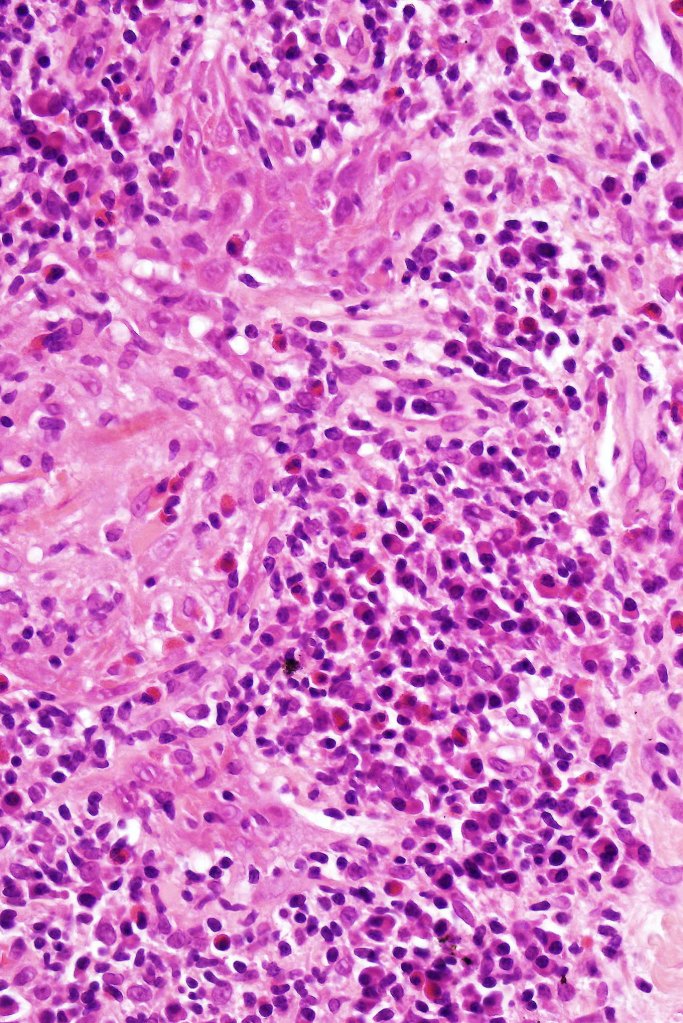

Histological features

•Follicular infiltration by atypical lymphocytes & Sézary cells

•Eosinophils sometimes conspicuous (eosinophilic folliculitis-like appearance)

•Granulomatous inflammation secondary to follicular destruction

•Large cell transformation occasionally present